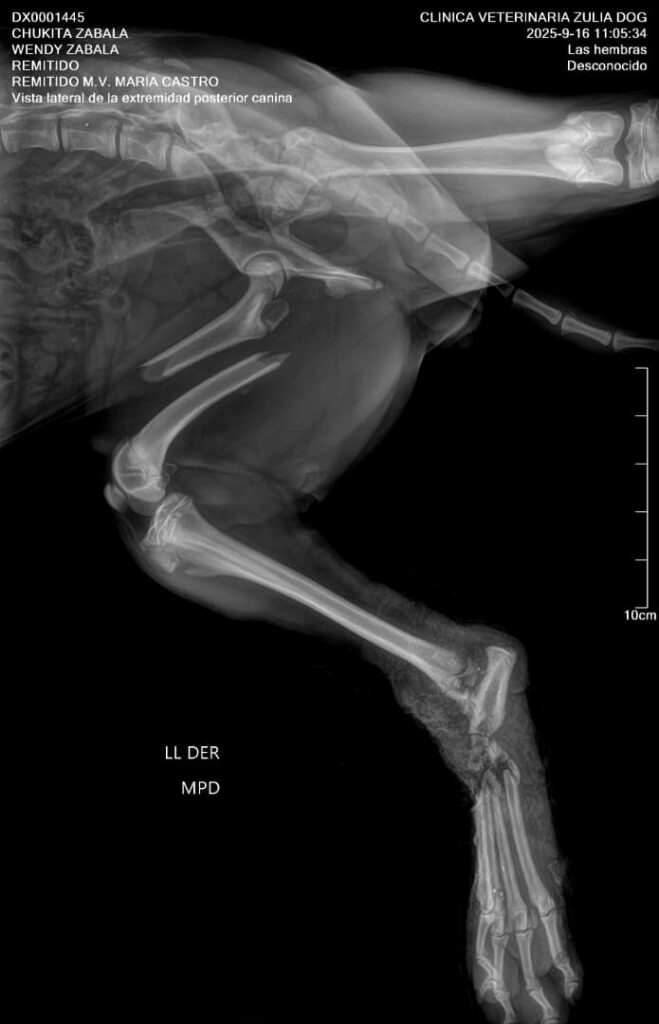

La perrita presenta una doble fractura: una en la pata de arriba, cerca de la cadera, y la otra en la parte de abajo, que está completamente partida.